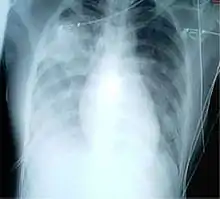

A chest radiograph is frequently used in diagnosis.[23] In people with mild disease, imaging is needed only in those with potential complications, those not having improved with treatment, or those in which the cause is uncertain.[23][67] If a person is sufficiently sick to require hospitalization, a chest radiograph is recommended.[67] Findings do not always match the severity of disease and do not reliably separate between bacterial and viral infection.[23]

X-ray presentations of pneumonia may be classified as lobar pneumonia, bronchopneumonia, lobular pneumonia, and interstitial pneumonia.[73] Bacterial, community-acquired pneumonia classically show lung consolidation of one lung segmental lobe, which is known as lobar pneumonia.[41] However, findings may vary, and other patterns are common in other types of pneumonia.[41] Aspiration pneumonia may present with bilateral opacities primarily in the bases of the lungs and on the right side.[41] Radiographs of viral pneumonia may appear normal, appear hyper-inflated, have bilateral patchy areas, or present similar to bacterial pneumonia with lobar consolidation.[41] Radiologic findings may not be present in the early stages of the disease, especially in the presence of dehydration, or may be difficult to interpret in the obese or those with a history of lung disease.[24] Complications such as pleural effusion may also be found on chest radiographs. Laterolateral chest radiographs can increase the diagnostic accuracy of lung consolidation and pleural effusion.[40]